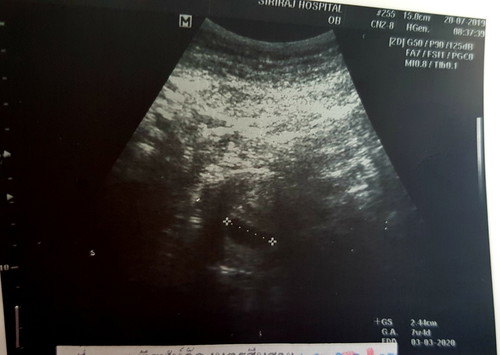

U/S ผ่านหน้าท้อง 6 Weeks ไม่เห็นตัวเด็ก

ปกติไหมคะ เห็นถุงตั้งครรภ์ 2.4 cm. อายุครรภ์ในเครื่องบอกว่า 7 w. แต่จริงๆคือ 6 w ไม่เห็นอะไรเลย นอกจากถุงตั้งครรภ์ หมอนัดอีกทีอีกสองสัปดาห์ค่ะ